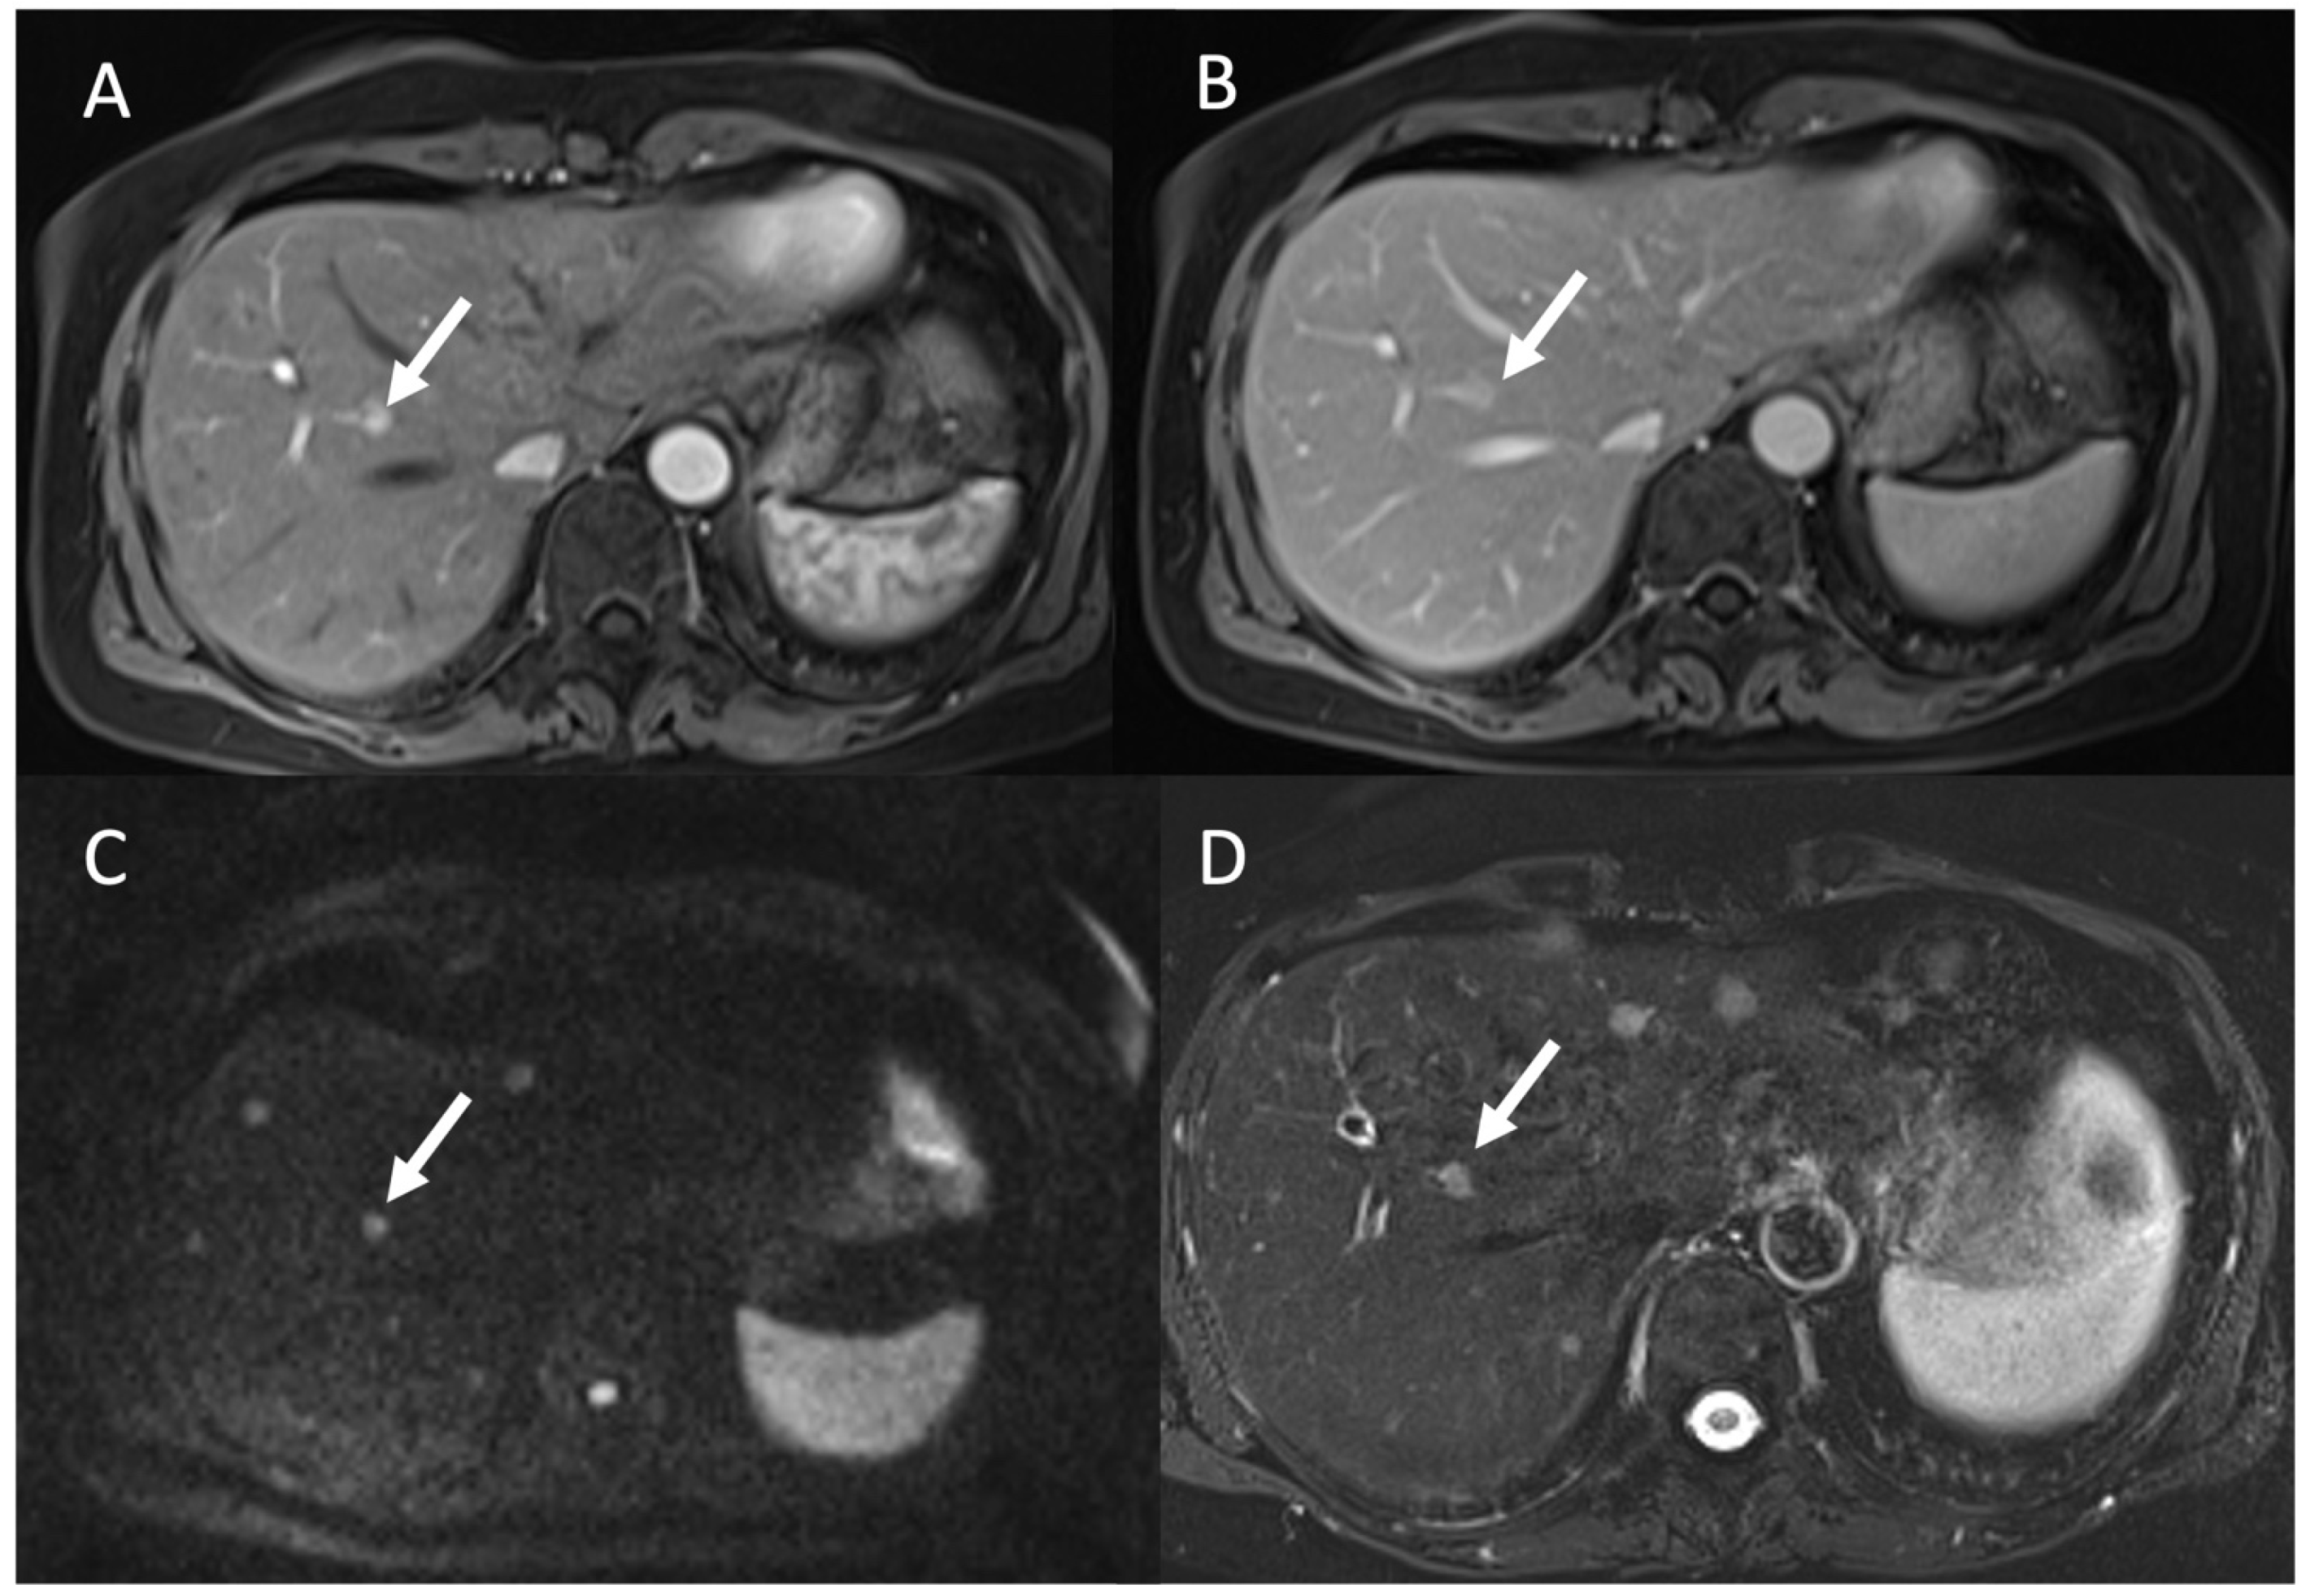

- Granata, V.; Grassi, R.; Fusco, R.; Setola, S.; Belli, A.; Ottaiano, A.; Nasti, G.; La Porta, M.; Danti, G.; Cappabianca, S.; et al. Intrahepatic cholangiocarcinoma and its differential diagnosis at MRI: How radiologist should assess MR features. Radiol. Med. 2021, 126, 1584–1600. [Google Scholar] [CrossRef] [PubMed]

- Renzulli, M.; Brandi, N.; Argalia, G.; Brocchi, S.; Farolfi, A.; Fanti, S.; Golfieri, R. Morphological, dynamic and functional characteristics of liver pseudolesions and benign lesions. Radiol. Med. 2022, 127, 129–144. [Google Scholar] [CrossRef] [PubMed]

- Granata, V.; Fusco, R.; Maio, F.; Avallone, A.; Nasti, G.; Palaia, R.; Albino, V.; Grassi, R.; Izzo, F.; Petrillo, A. Qualitative assessment of EOB-GD-DTPA and Gd-BT-DO3A MR contrast studies in HCC patients and colorectal liver metastases. Infect. Agent. Cancer 2019, 14, 1–9. [Google Scholar] [CrossRef]

- Granata, V.; Fusco, R.; Avallone, A.; Filice, F.; Tatangelo, F.; Piccirillo, M.; Grassi, R.; Izzo, F.; Petrillo, A. Critical analysis of the major and ancillary imaging features of LI-RADS on 127 proven HCCs evaluated with functional and morphological MRI: Lights and shadows. Oncotarget 2017, 8, 51224. [Google Scholar] [CrossRef]